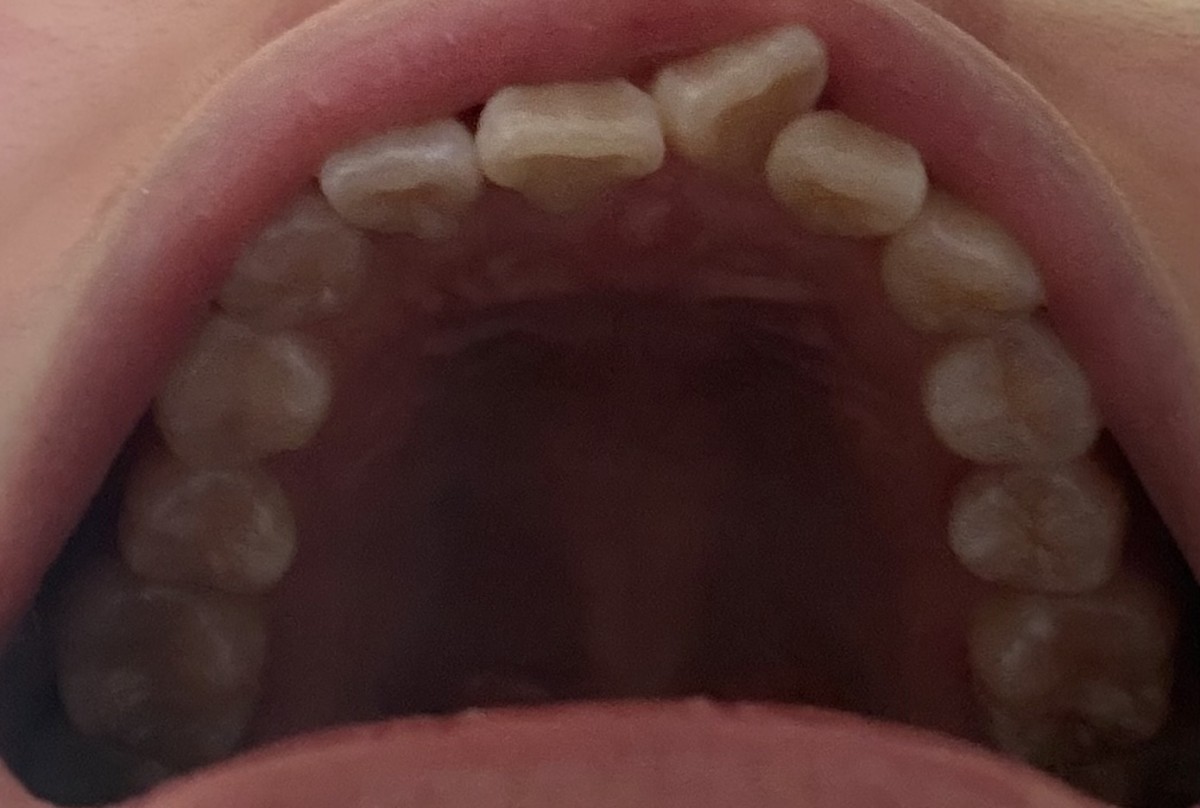

윗니 하나가 틀어져 있는데 부분 교정 가능할지 문의드립니다!